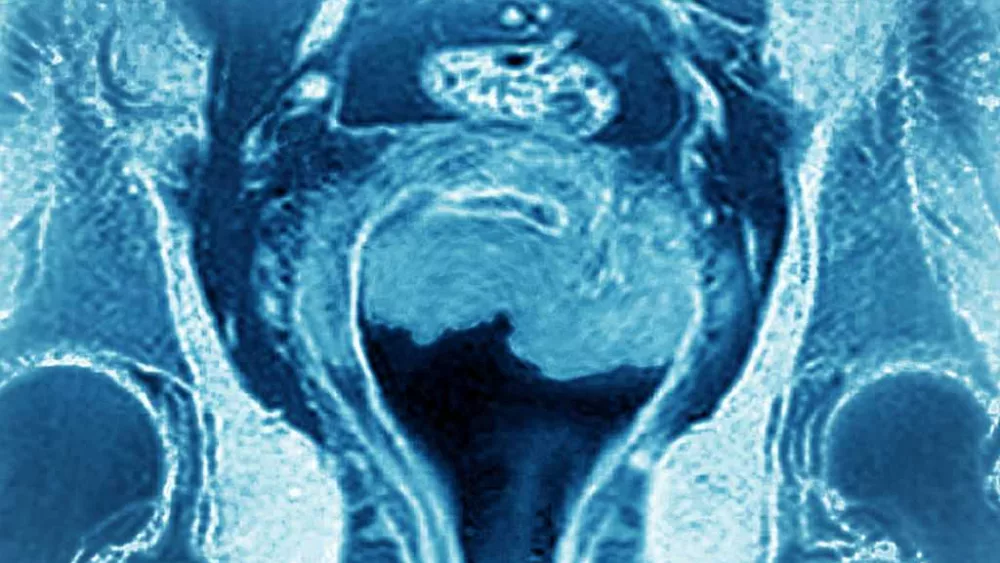

Uterine cancer is one of the most common forms of cancer, and there are two distinct types.